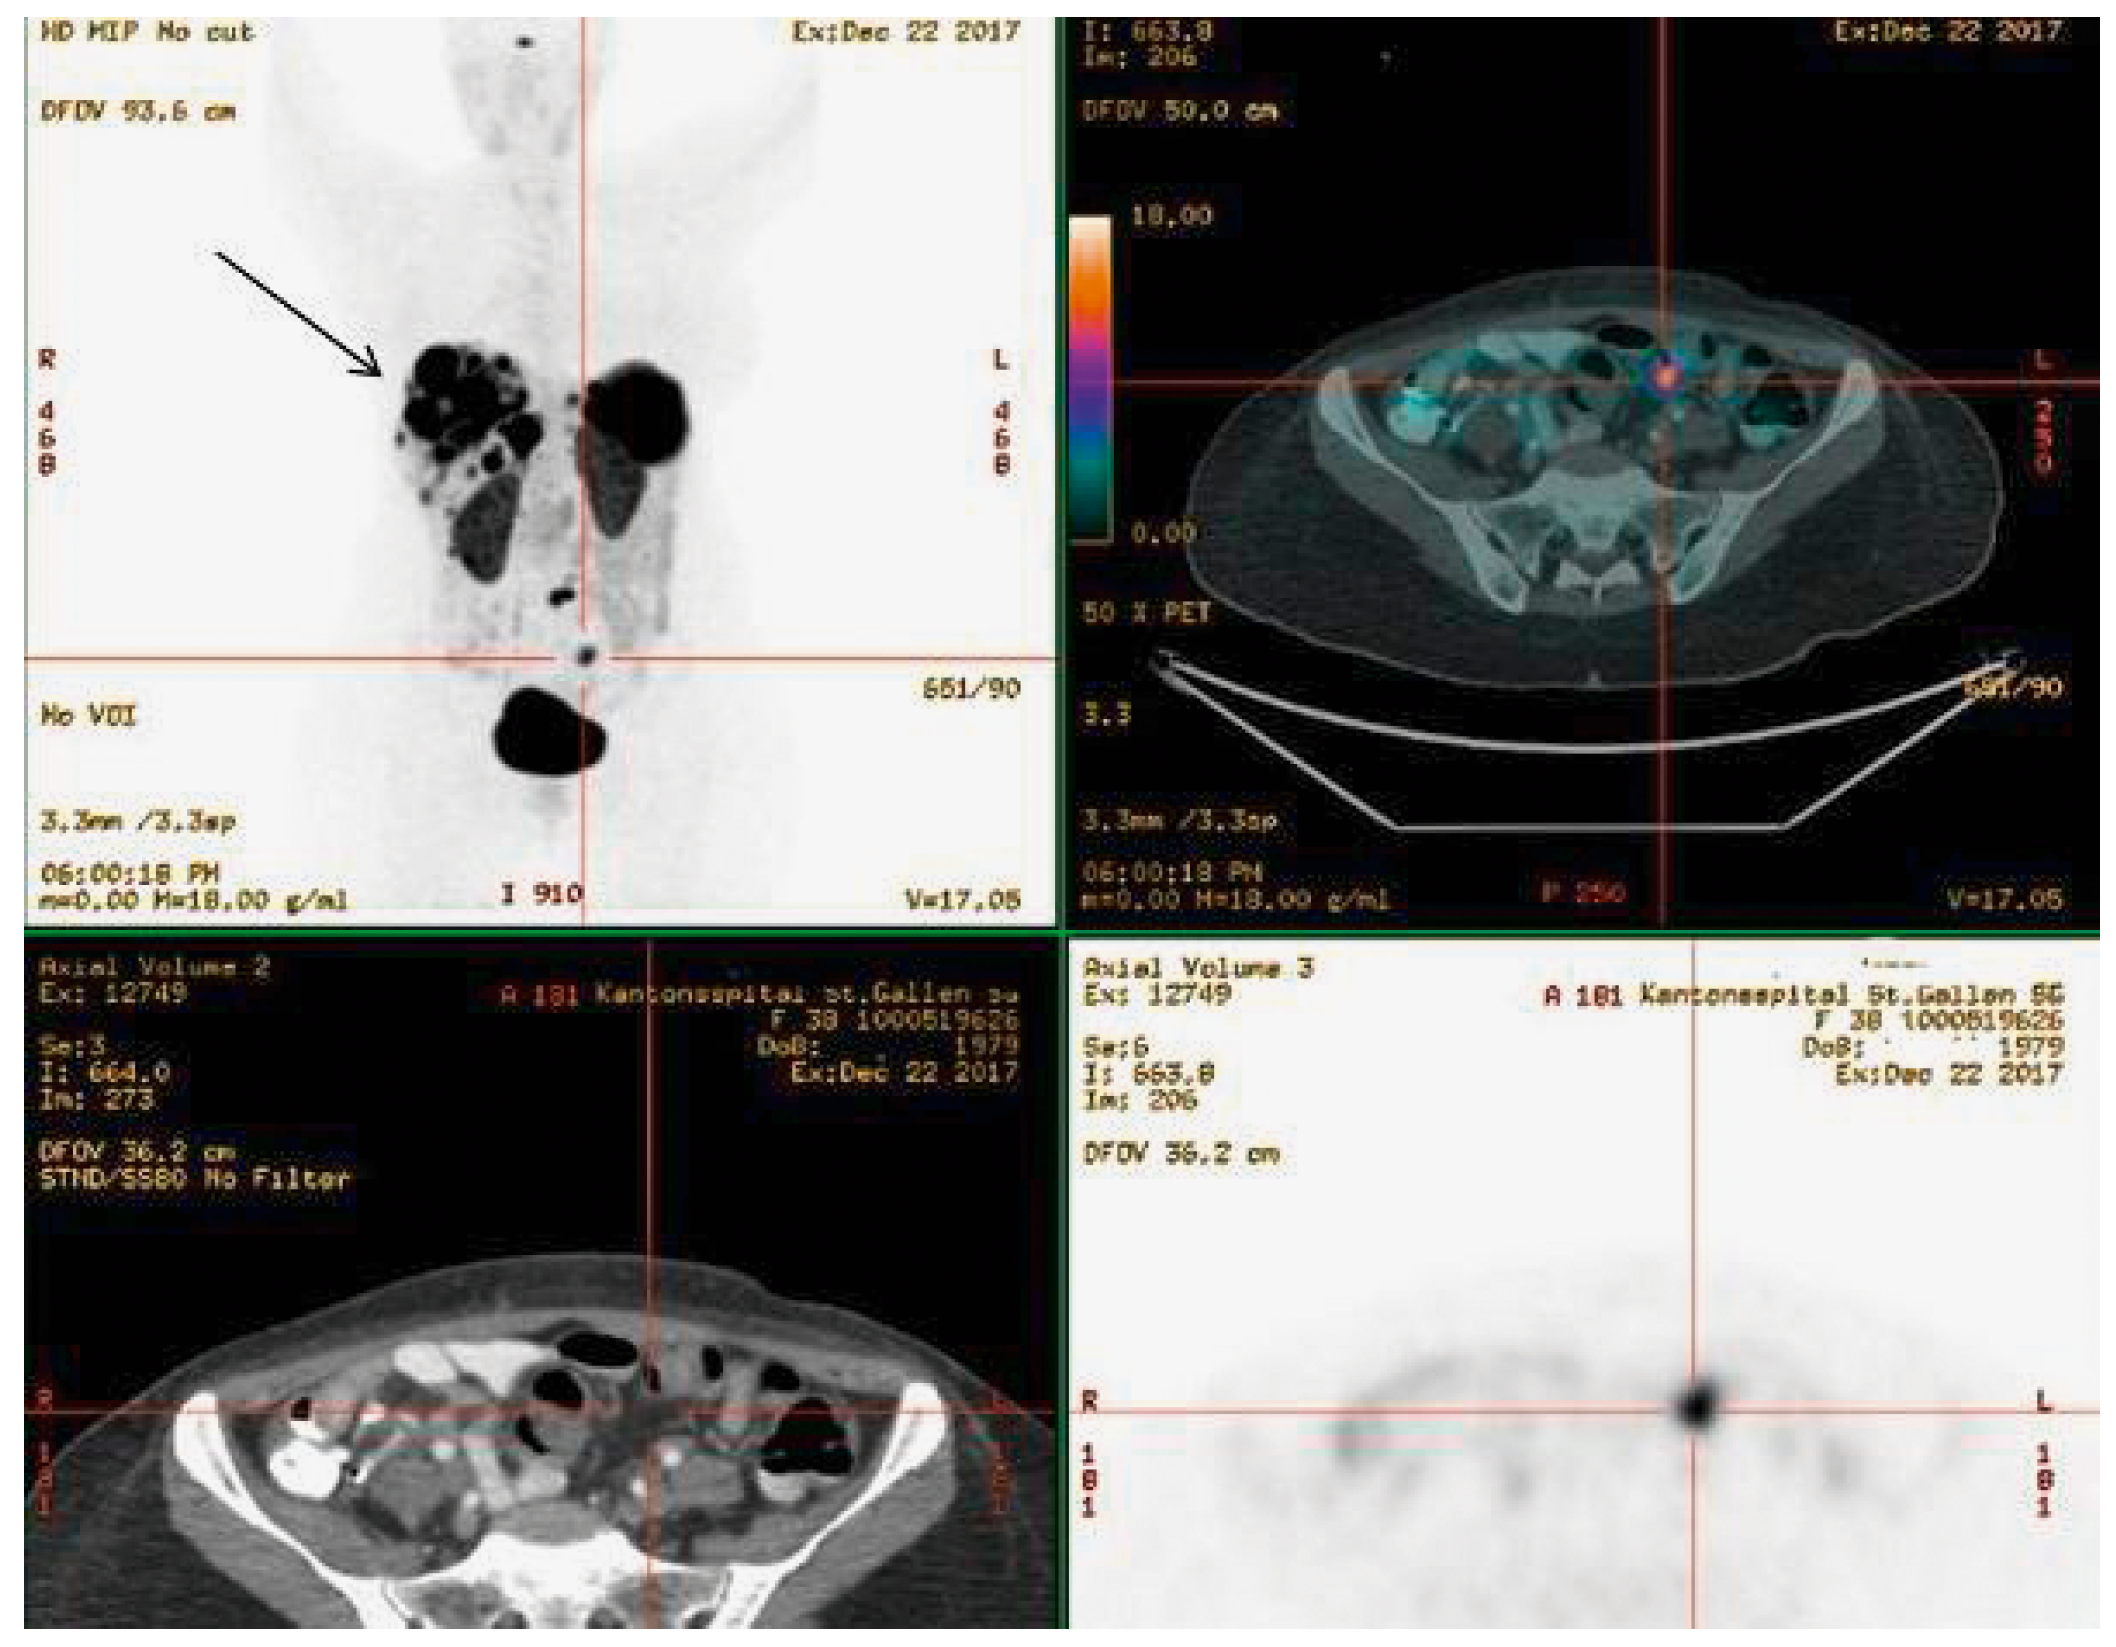

A 66-year old female was hospitalized in our Cardiovascular Department for a first episode of syncope. Clinical history revealed smoking and hypercholesterolemia. The baseline ECG showed repetitive non-sustained ventricular tachycardia (VT) of rather narrow QRS duration originating from the infero-basal interventricular septum (IVS) or from the right moderator band (Figure 1). A coronary angiography revealed a 50–70% stenosis of the left main coronary artery treated with the implantation of an active stent.The echocardiography was non-contributive, but the cardiac MRI revealed a localized thickening of the inferior IVS (Figure 2A) with hyperintense inhomogeneous appearance on T2-weighted images (Figure 2B) confirmed by elevated T2 values (60 ms, normal values <55 ms; Figure 2D) and T1 values (1184 ms, normal values <1050 ms; Figure 2C); the high signal intensity on late gadolinium enhancement (LGE, Figure 2E-2F) was indicative of a large interstitial space secondary to edema (high T2 and T1 values) and hypervascularization. The following differential diagnoses were considered: cardiac sarcoidosis, metastatic tumor or infectious disease. Endomyocardial biopsy samples taken from the IVS did not show any malignant cells or granuloma. An electrophysiological study did not show any susceptibility to sustained ventricular arrhythmias. The unexplained 8-Kg weight lost over the past year in a smoker patient raised the suspicion of malignancy. An 18FDG-PET scan performed after a 24-hour carbon hydrate free diet revealed a focal hypermetabolic activity within the IVS at the site of LGE (Figure 2G). Interestingly, a hypermetabolic nodule in the upper lobe of the right lung (Figure 2H) together with active paratracheal lymph nodes were suggestive of a metastatic lung cancer, that was confirmed by cytoponction of paratracheal lymph nodes (non-small cell lung cancer: NSCLC). The patient started a combination chemotherapy with carboplatin and pemetrexed and now is followed by the oncologists and the cardiologists.

Conclusions: this clinical case represents an unusual manifestation of lung cancer (NSCLC) with cardiac metastasis presenting with repetitive non-sustained ventricular tachycardia. In this patient, cardiac MRI allowed to detect the cardiac metastasis and was useful to guide the endomyocardial biopsy and the elettrophysiological study.